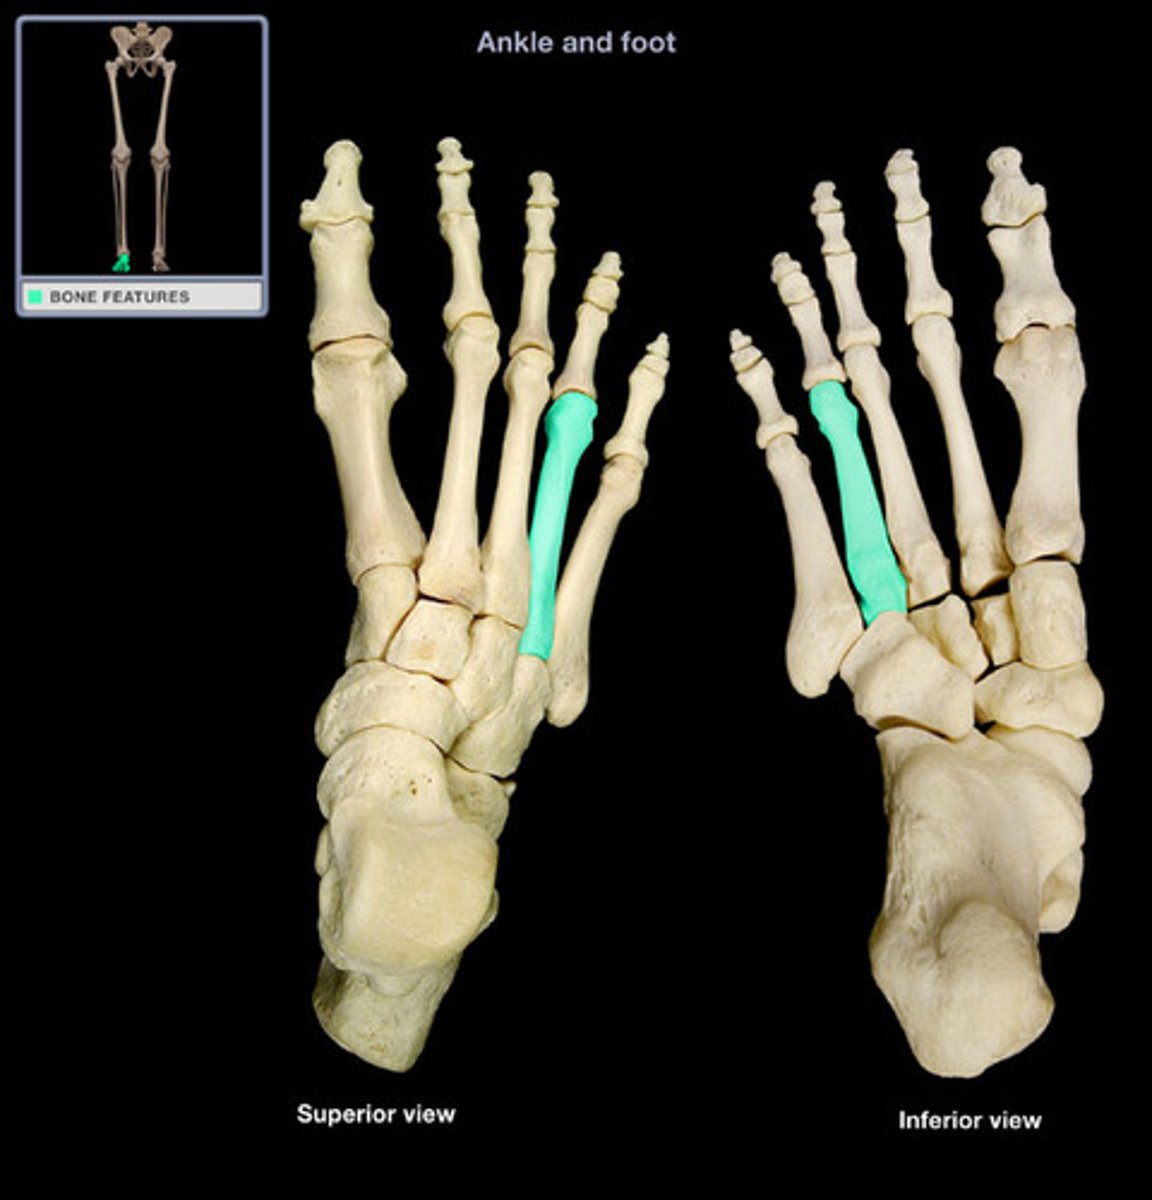

Fourth metatarsal